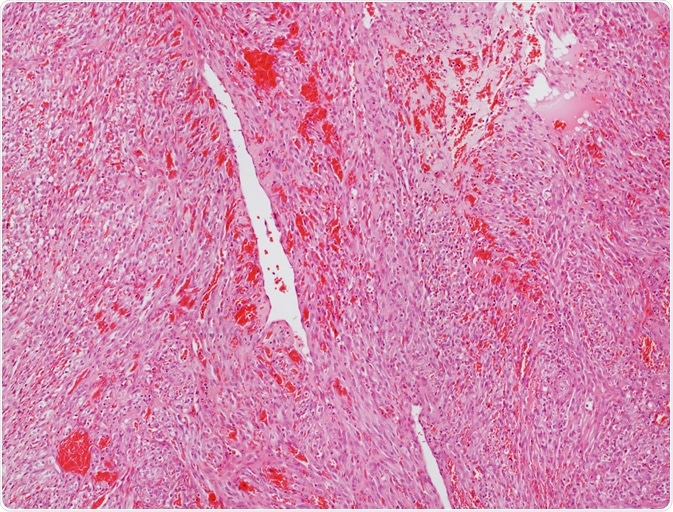

Angiosarcoma is a type of soft tissue tumor that originates from the vascular endothelial cells which form the inner lining of blood as well as lymphatic vessels. This sarcoma is rare, but malignant in nature and affects any part of the body, especially, the skin, liver, breast, and deep tissues.

angiosarcomaMicroscope picture of an angiosarcoma. Image Credit: Convit / Shutterstock.com